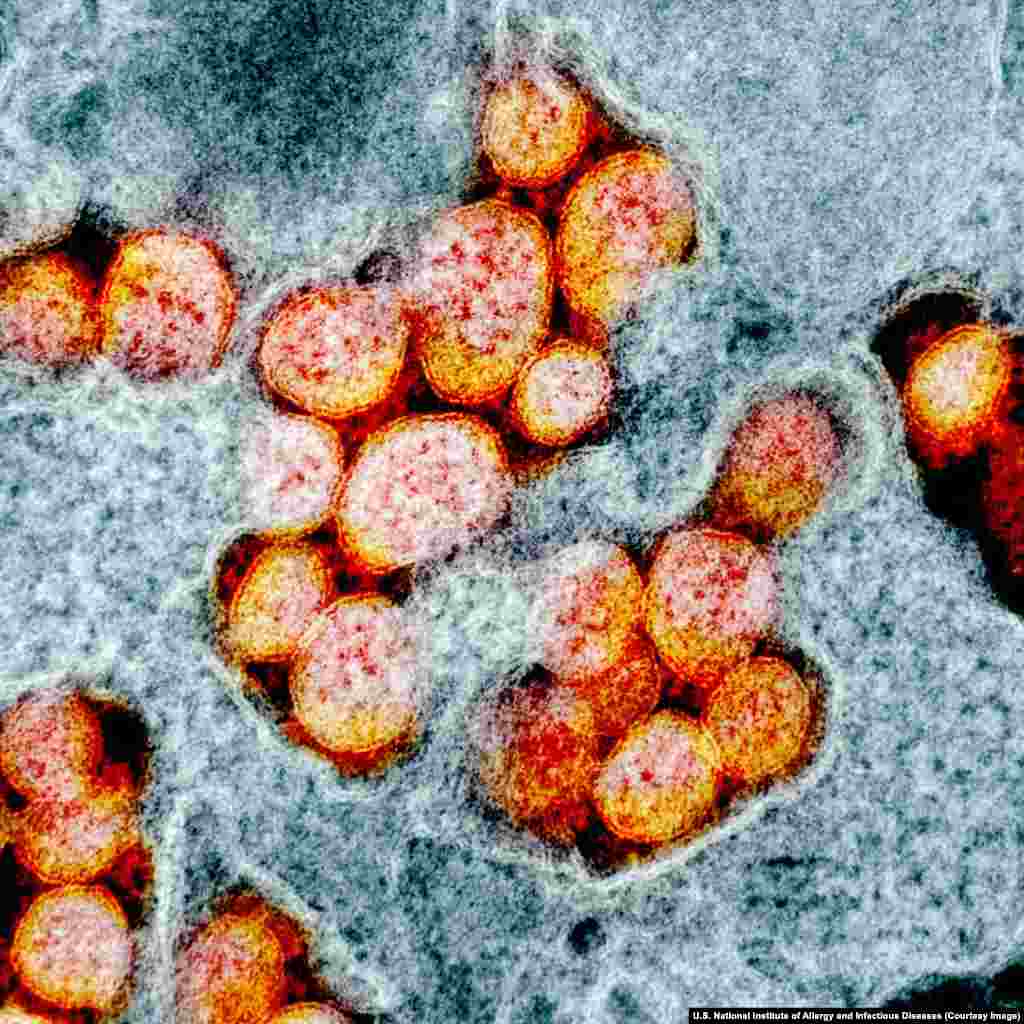

6

Скопление вирионов SARS-CoV-2, которое видно через электронный микроскоп.

Вирионы коронавируса с помощью шипов на своей поверхности прикрепляются к рецепторам в некоторых клетках человеческого организма – особенно в легких – и проникают затем внутрь клетки.

Вирионы коронавируса с помощью шипов на своей поверхности прикрепляются к рецепторам в некоторых клетках человеческого организма – особенно в легких – и проникают затем внутрь клетки.

7

Попав внутрь, вирус высвобождает генетический материал, который эффективно обманывает клетку и продолжает вторжение в организм. Масса вирионов прорывается сквозь клеточную стенку и поражает другие клетки. Этот момент изображен здесь на примере клетки пациента, инфицированого COVID-19, в США.

8

Диаметр вириона – около 120 нанометров. Это означает, что на маленьком участке, сопоставимом со срезом человеческого волоса, может уместиться около 750 вирионов.